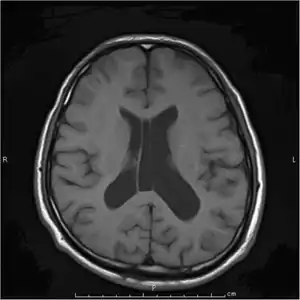

The most significant issue regarding the Todd's paresis is its differentiation from a stroke. The issue is further complicated by the fact that some strokes trigger a focal seizure during the acute phase. A Todd's paresis in this context may overestimate the extent of neurological deficit due to the vascular process itself resulting in erroneous decisions with regards to acute stroke therapy such as thrombolysis. For this reason a seizure during an acute stroke is generally accepted to be a relative contraindication to thrombolytic therapy, especially in the absence of documented cerebrovascular occlusion using vascular imaging techniques.[8]